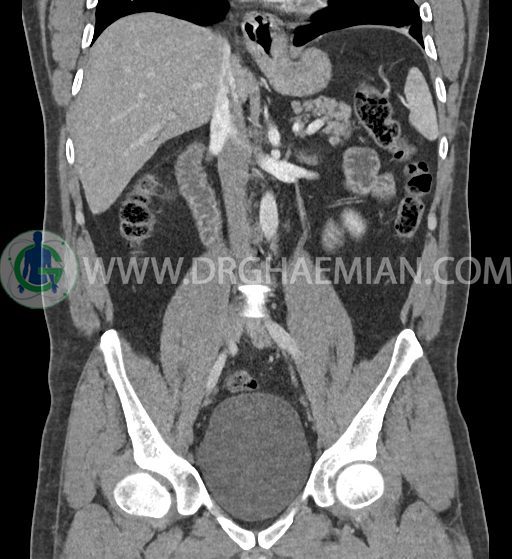

سی تی اسکن شکم و لگن با استفاده از اشعات ایکس تصاویر عرضی از ناحیه شکم و لگن ایجاد میکند. در این کیس فتق هیاتوس و هیدرویورترونفروز دیده می شود.

در سی تی اسکن اسپیرال شکم و لگن با کنتراست خوراکی و وریدی (مولتی دیدکتور 16 با مقاطع ظریف و بازسازی های ساژیتال و کرونال) :

ضایعه ای در کبد، کیسه صفرا، مجاری صفراوی، طحال، کلیه ها، پانکراس و آدرنالها مشهود نیست.

-sliding hiatal hernia به ابعاد 60x44mm با جابجایی JE.junction و فوندوس معده به فضای مدیاستن خلفی دیده می شود.